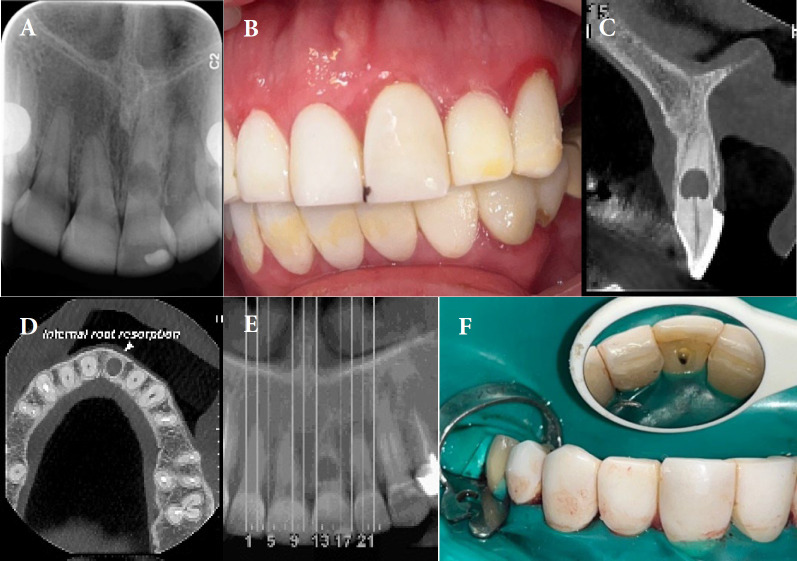

Internal inflammatory root resorption (IRR) poses significant challenges in endodontic treatment due to its potential to compromise tooth integrity. This case report describes the conservative management of IRR in a 40-year-old woman with a radiolucent lesion in the midroot of a maxillary central incisor. Early diagnosis using cone-beam computed tomography prevented perforation and guided treatment planning. Non-surgical endodontic treatment was performed using a dental operating microscope, ultrasonic irrigation, and a hybrid obturation technique. The apical portion of the canal was sealed with a bioceramic sealer and single-cone gutta-percha, while the resorptive defect was filled with calcium-enriched mixture cement due to its biocompatibility and sealing properties. At one-year follow-up, the patient was asymptomatic, with radiographic evidence of healing. This case highlights the efficacy of combining advanced diagnostic tools, bioactive materials, and minimally invasive techniques for successful IRR management.